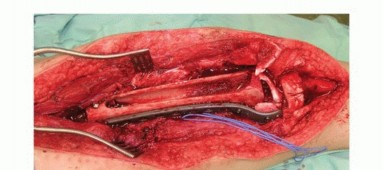

استئصال الورم أو الأنسجة التالفة

يُزال الورم العظمي وفقًا للتقنيات القياسية، وتُقاس طول وقطر العيب العظمي البيني الناتج (TECH FIGS 2,3,4).

استئصال ورم الجذع

يُستأصل ورم الجذع بهوامش واسعة، تاركًا عيبًا عظميًا بينيًا طويلاً.

استئصال ساركوما عظمية

- أ. صورة